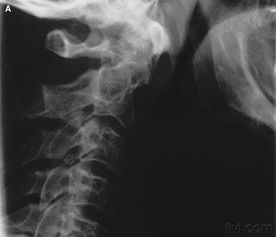

因為頸骨骨折也就是頸部脊椎骨的骨 折,在脊椎骨中央有神經(jīng)通過(guò),這些神經(jīng)像電纜一樣能把大腦的命令傳達到全身,又能把身體的感覺(jué)傳向大腦。如果骨折切斷或壓迫脊椎骨中的神經(jīng),頸以下就會(huì )完 全麻痹,有時(shí)會(huì )使呼吸停止。

3、頸椎骨折常見(jiàn)于跳水誤跳入淺游泳池,或從很高的地方墜落以及交通事故等。